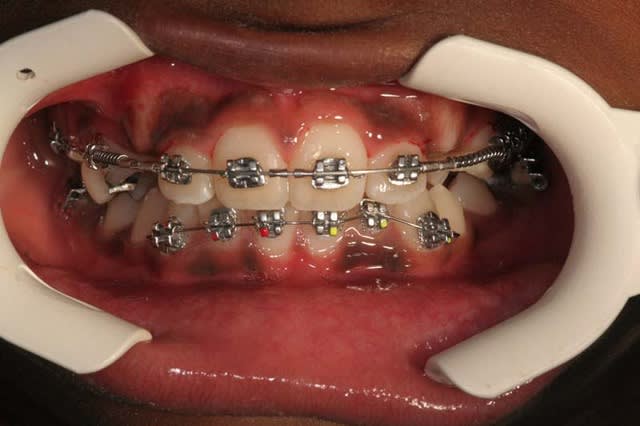

par exemple

Depart 1 y9ttvq - Eugenol

Materiel  1 efp0tb - Eugenol

voici les photos du m jour

bouche fermée

bouche ouverte

arcades

@+ Bjc.